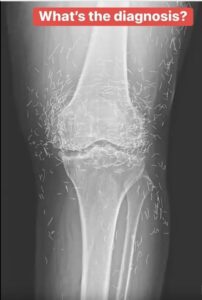

Years later, when doctors took X-rays to evaluate her knee condition, they weren’t prepared for what appeared on the images. Her knees were filled with dozens of bright, metallic flecks — tiny needles embedded deep within the joint area.

The findings were later documented in a case published by the New England Journal of Medicine.